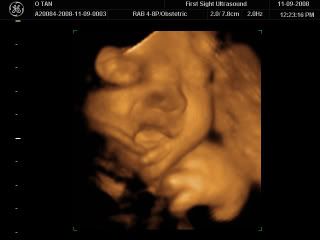

So back to baby Caleb! We went for our long waited 3D/4D scan today for our 2nd year wedding anniversary and 4 years since we knew each other gift! The scan was super amazing! By the way, the sonographer turned out to be my Yoga classmate, Leslie... Haha what a coincidence!

Baby Caleb was really really very cooperative during the scan, he was so alert and his eyes were wide open... Leslie was saying that most babies will be sleeping or have their eyes closed! The package was really worth it. It was $120 but they had 10% off for military personnel and so we only paid $108! We had 20 over minutesworth of time to see baby Caleb and were given a CD with all of baby Caleb's pictures and a DVD of his movements with music at the end of it, I don't really know how to extract the DVD video though so here are just pictures of him to share!

Here's a picture of him rubbing the back of his hand against his lips and a few times he even sucked on it! Super cute!